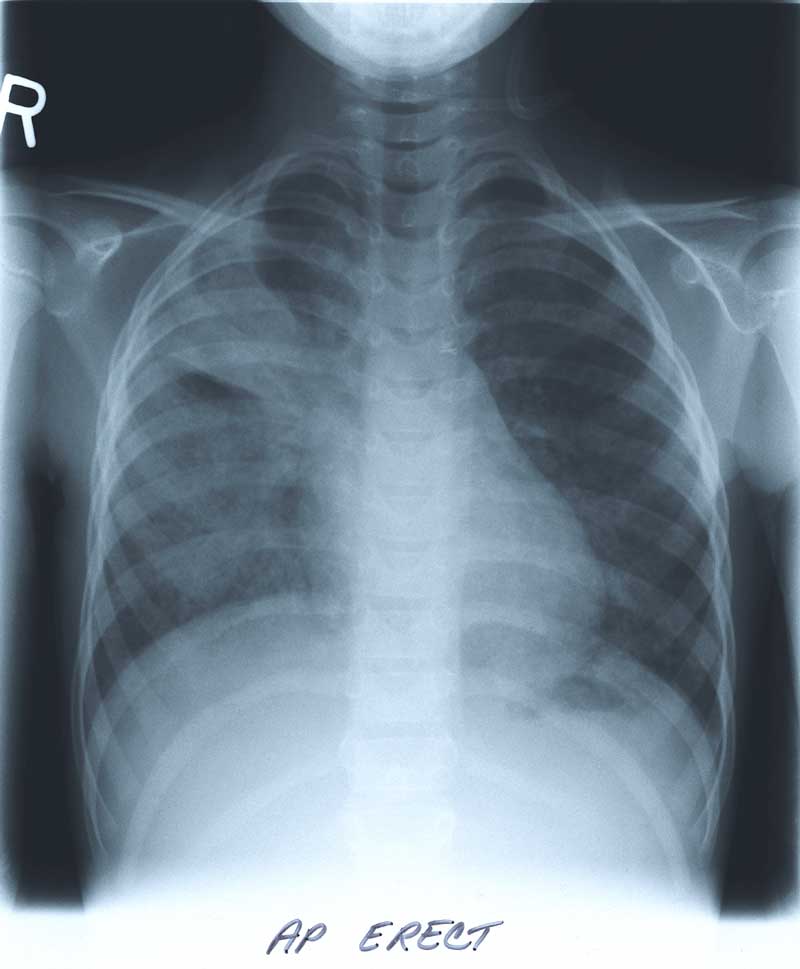

"Ongoing oxygen requirements after a pneumonia."

A six and half year old female presented with a five day history of

pleuritic chest pain, fever, and cough in April 1998. She had no hemoptysis.

The initial physical examination in April 1998 revealed, a child in mild respiratory distress, with cyanosis in room air. She was tachycardic, tachypneic and febrile. She was a thin girl (~5% for height and weight), with dry skin.

The respiratory examination revealed dullness to percussion in the right upper lobe, crackles and wheeze bilaterally. There was no clubbing and the rest of her examination was normal.

BELOW

is her CHEST X-RAY taken during the hospitalization.

Previous films from her NICU stay are not available.

Enlarge the CHEST X-RAY LEFT, enlarge the chest x-ray RIGHT.

WHAT ARE YOUR FINDINGS?